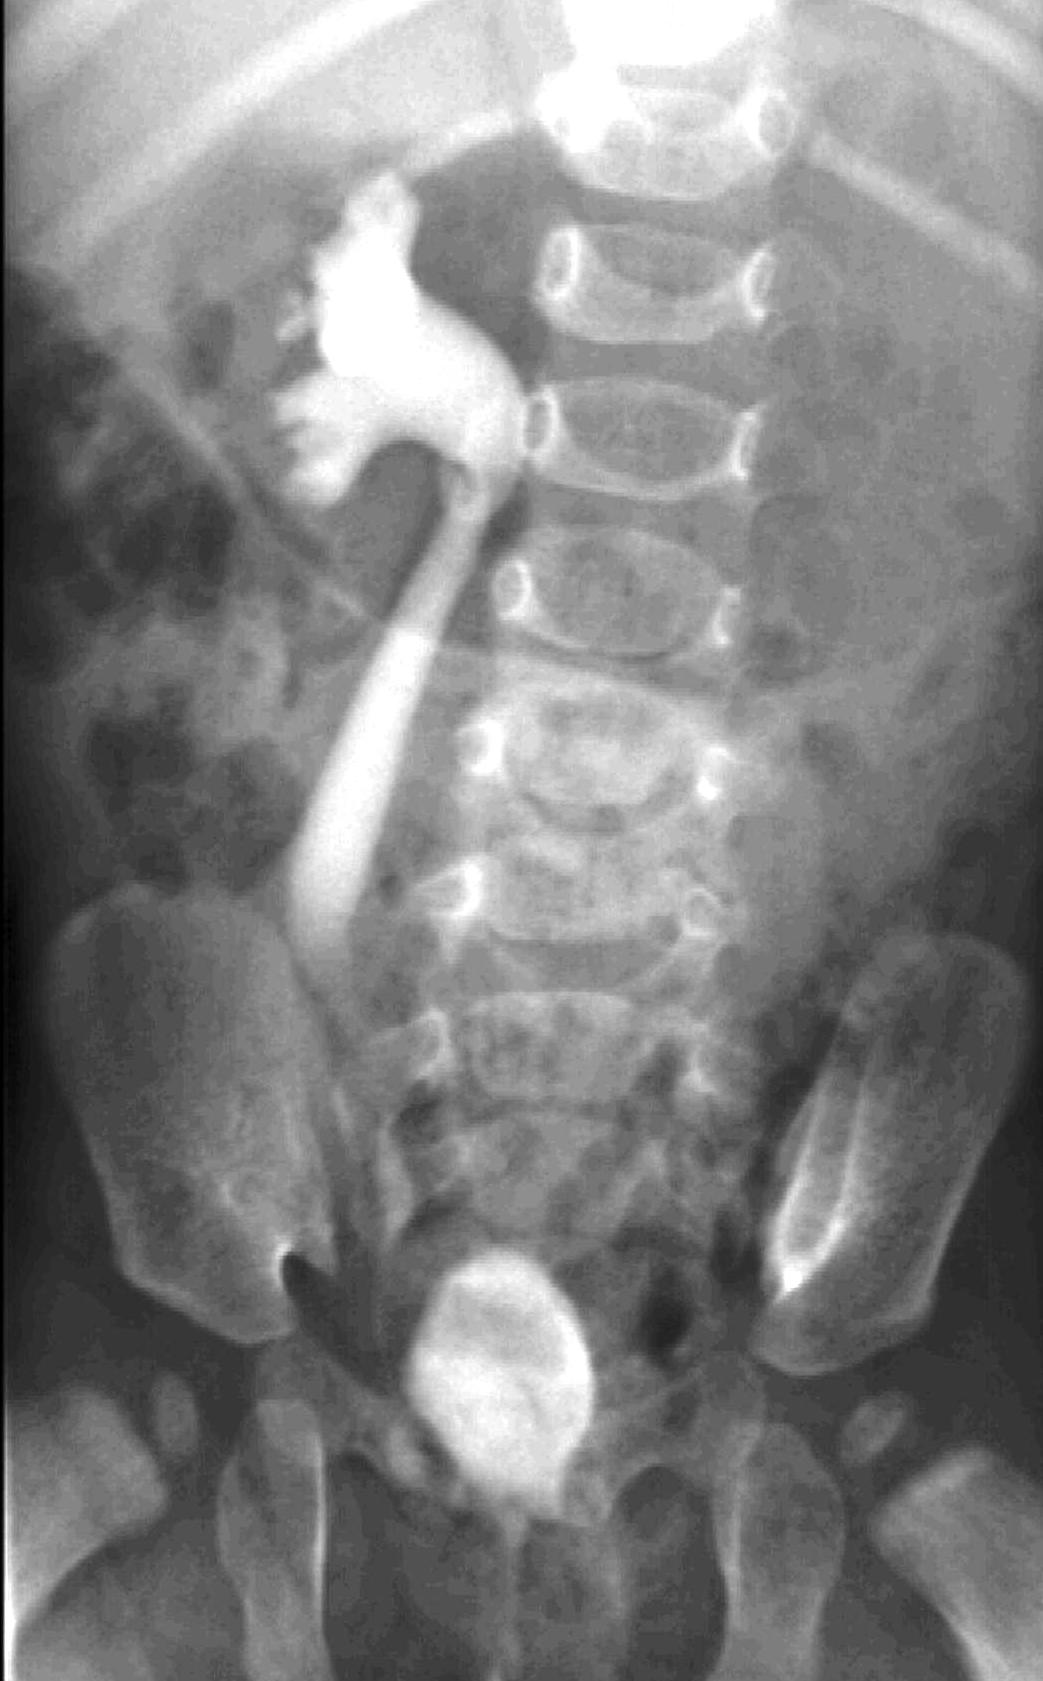

Image

22.The calices and the pyelon of the kidney are markedly dilated, the parenchyma is thinner. Severe hydronephrosis. The ureter is not visible. Pyelouretral stenosis.